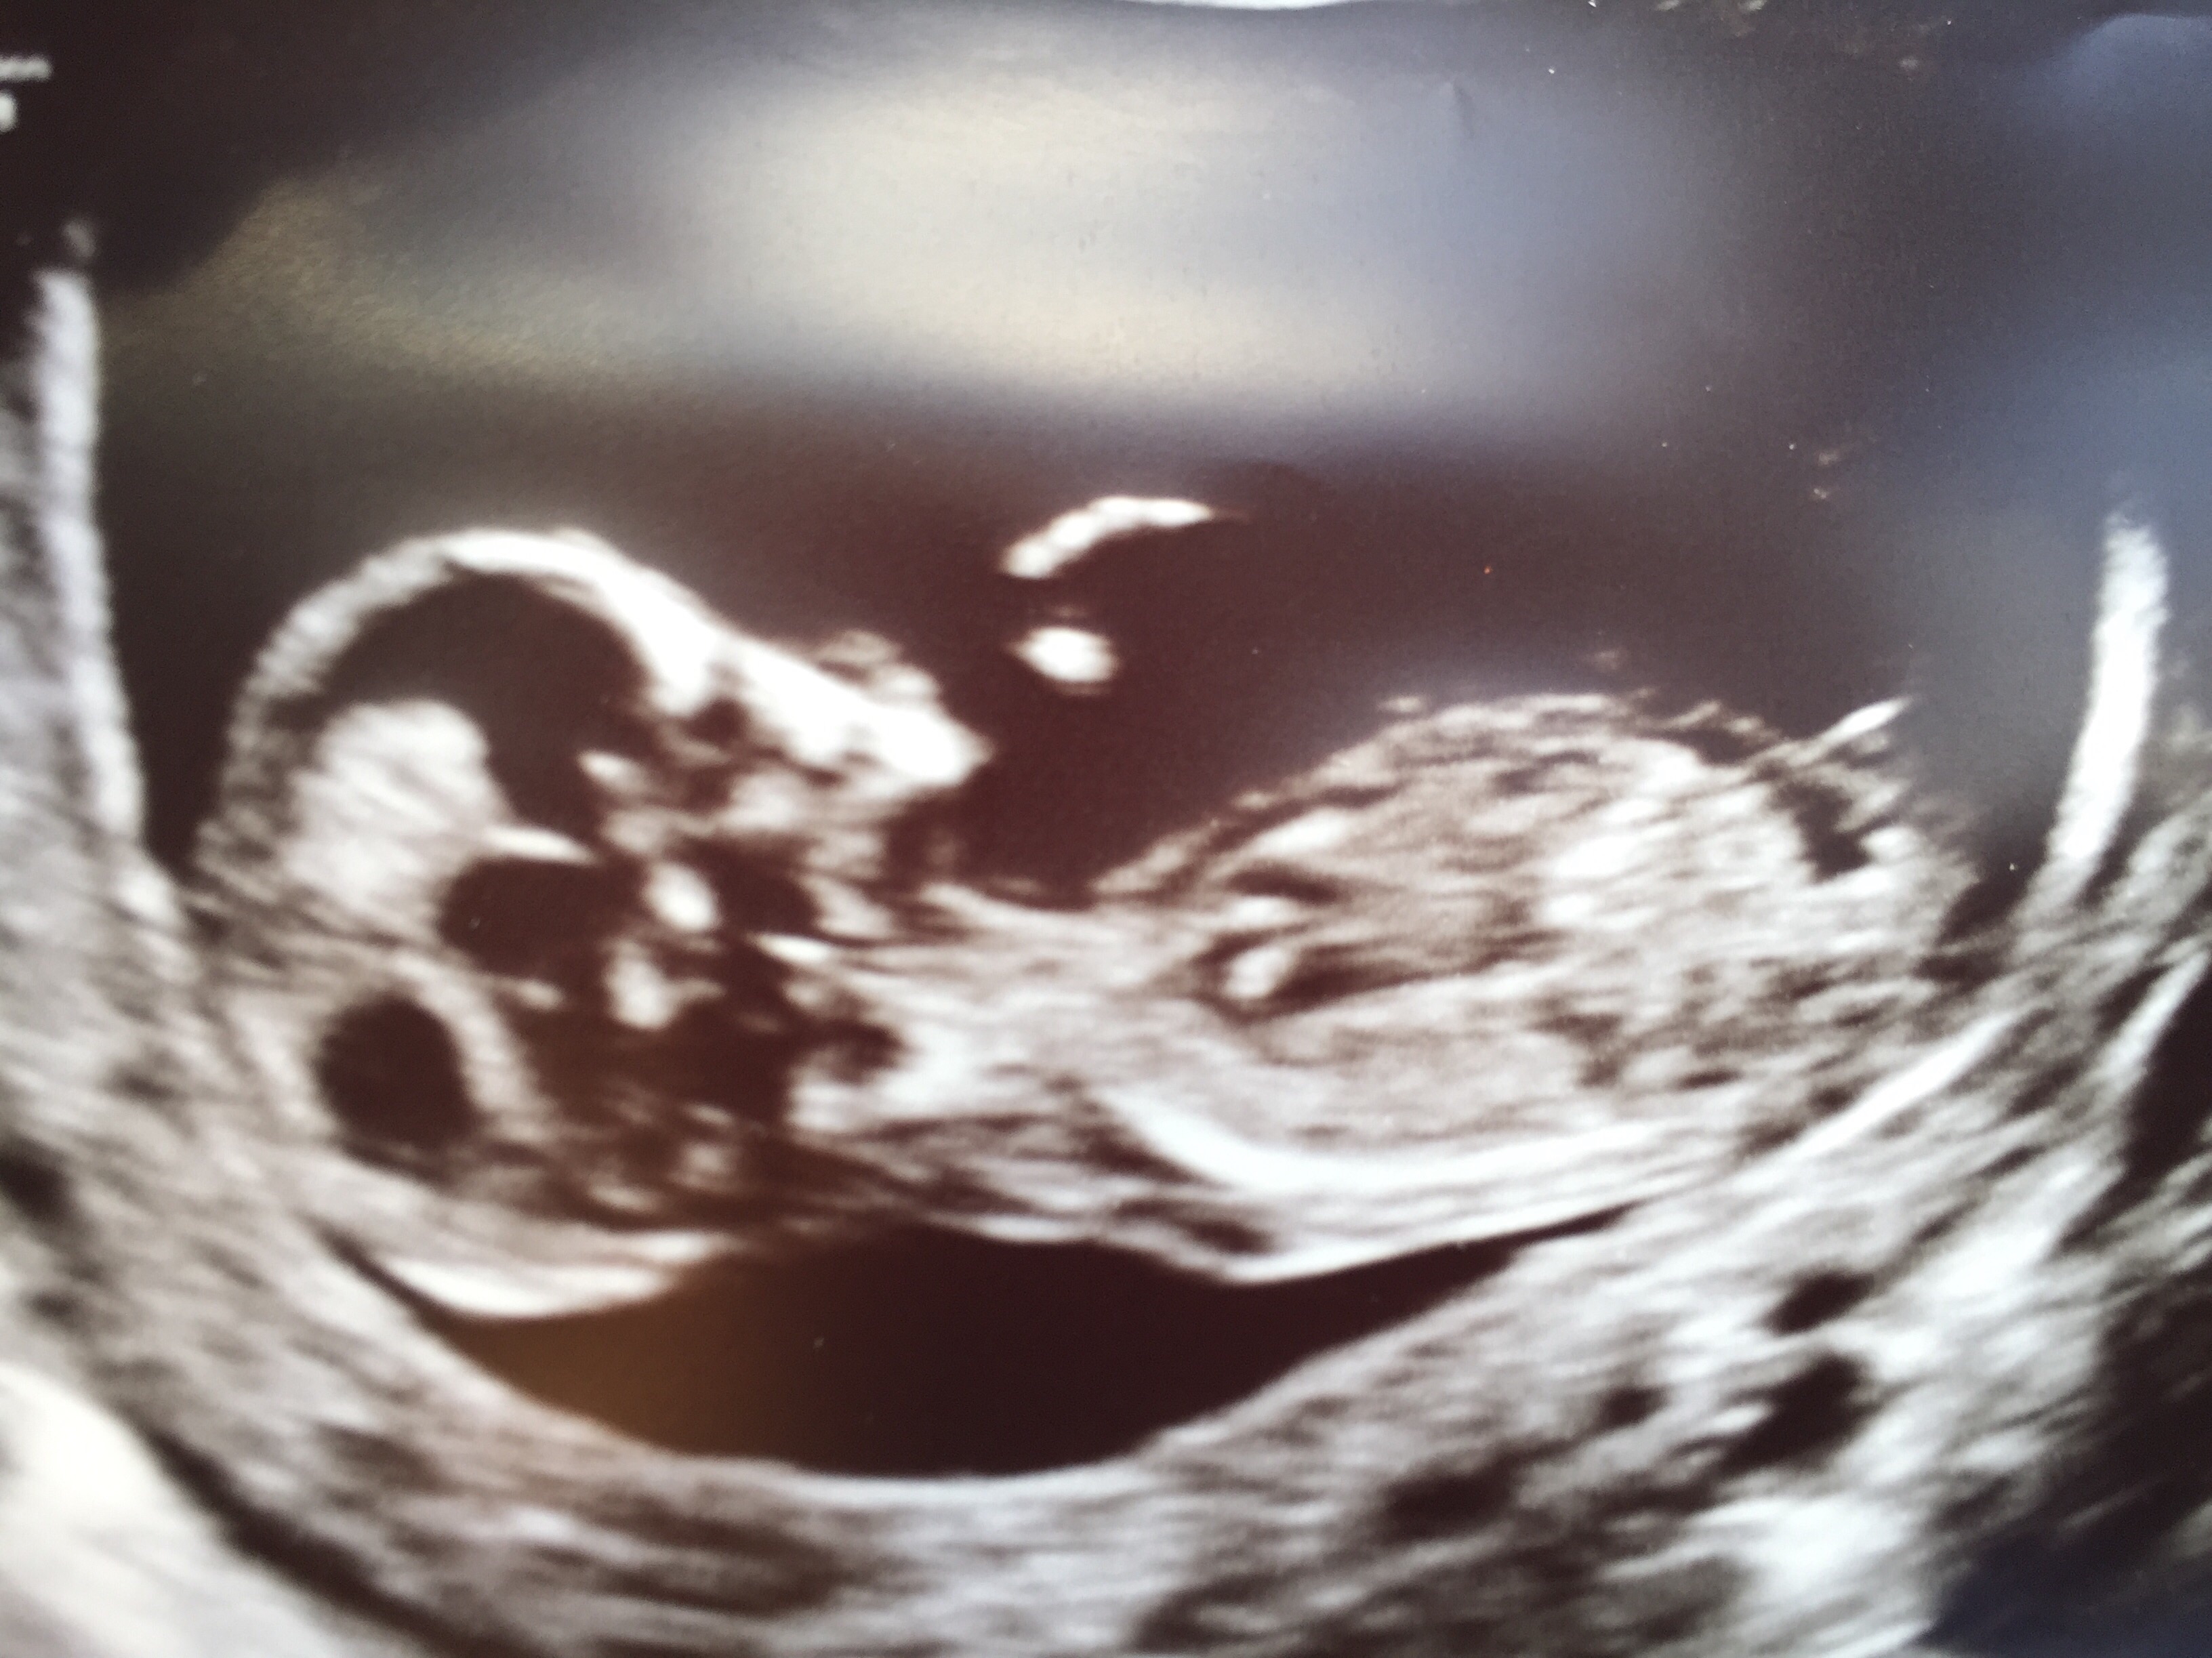

hi all! This is my first time starting a thread and I know there have been a bunch of scans posted, but just wanted to share my little peanut!

The scan went well and she said all the measurements are on track. Still need to wait for the blood test, but I am hesitantly relieved!

I am finally starting to feel like this is really happening. The little one was wiggling around and waving, and even had their little leg sticking up which had the tech laughing. I'm in love!